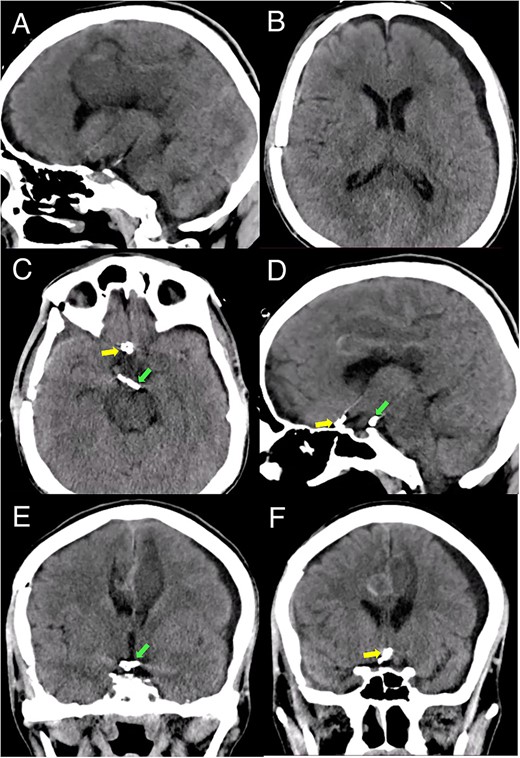

Postoperative course

Brain imaging demonstrated improvement of the hematoma and intraventricular hemorrhage with remnant postinfarction areas (Fig. 4). The patient was transferred to neurointensive care postoperatively, where he remained for 7 days. At this point, the neurological examination indicated he had 4/5 quadriparesis, a right third nerve paresis, and a GCS score of 13. Seven days later, he was discharged with a modified Rankin scale (mRS) score of 4. At the 1-month follow-up, the patient had a GCS of 14 and a mRS of 4. At the 3-month follow-up, the patient showed a significant improvement in the GCS score with a mRS of 2 and improved function of the right third cranial nerve.

Postoperative head CT. (A, B) Sagittal and axial views show resolution of the hematoma and intraventricular hemorrhage with remaining postinfarction areas. (C–F) Postoperative head CT views depict the placement of clips in the accessory A2 artery (yellow arrow) and basilar aneurysm (green arrow).